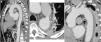

Na angioTC de controlo realizada um mês após a alta verificou‐se que tinha ocorrido rutura da íntima ao nível de uma das ulcerações da aorta e evolução para uma dissecção localizada, com imagem de pseudoaneurisma na porção proximal da aorta descendente, com dimensões de 27x51mm (figura 3). Face a isto, o doente foi novamente internado e, após discussão com cardiologia de intervenção e cirurgia cardiotorácica, foi decidido realizar tratamento percutâneo da aorta descendente (TEVAR), através da implantação de duas endopróteses (Valiant® 38x150mm e 34x150mm). A prótese proximal foi aposta à origem da artéria subclávia esquerda, sem condicionar compromisso do fluxo deste vaso, estendendo‐se a prótese distal até ao início da aorta abdominal, recobrindo‐se assim as ulcerações da aorta, o pseudoaneurisma, o canal arterial patente e a maior extensão do IMH. Na angioTC de controlo pós‐procedimento confirmou‐se o bom resultado da TEVAR e, distalmente à endoprótese distal, observou‐se uma imagem de dissecção da aorta abdominal, desde o tronco celíaco até ao nível da artéria mesentérica superior, sendo que estes dois vasos e as artérias renais tinham origem no verdadeiro lúmen (figura 4A, B e C). Não foi possível confirmar se esta dissecção estava já presente previamente à TEVAR, uma vez que a angioTC anteriormente efetuada tinha aquisição limitada à região torácica. Perante este achado, assumiu‐se uma estratégia conservadora.

AngioTC de controlo realizada 30 dias após a alta mostrando a evolução do IMH para dissecção e formação de um pseudoaneurisma com 27x51mm de maior diâmetro e colo de 23mm (A, B e C). O pseudoaneurisma localizava‐se ao nível da porção média da aorta descendente e a rutura da íntima teve origem na ulceração da parede da aorta que mostrara sinais de progressão na segunda angioTC. Imagem D: reconstrução tridimensional pela técnica de volume rendering da angioTC pós‐TEVAR, observando‐se as duas endopróteses parcialmente sobrepostas, recobrindo a aorta desde a artéria subclávia esquerda até ao início da aorta abdominal.